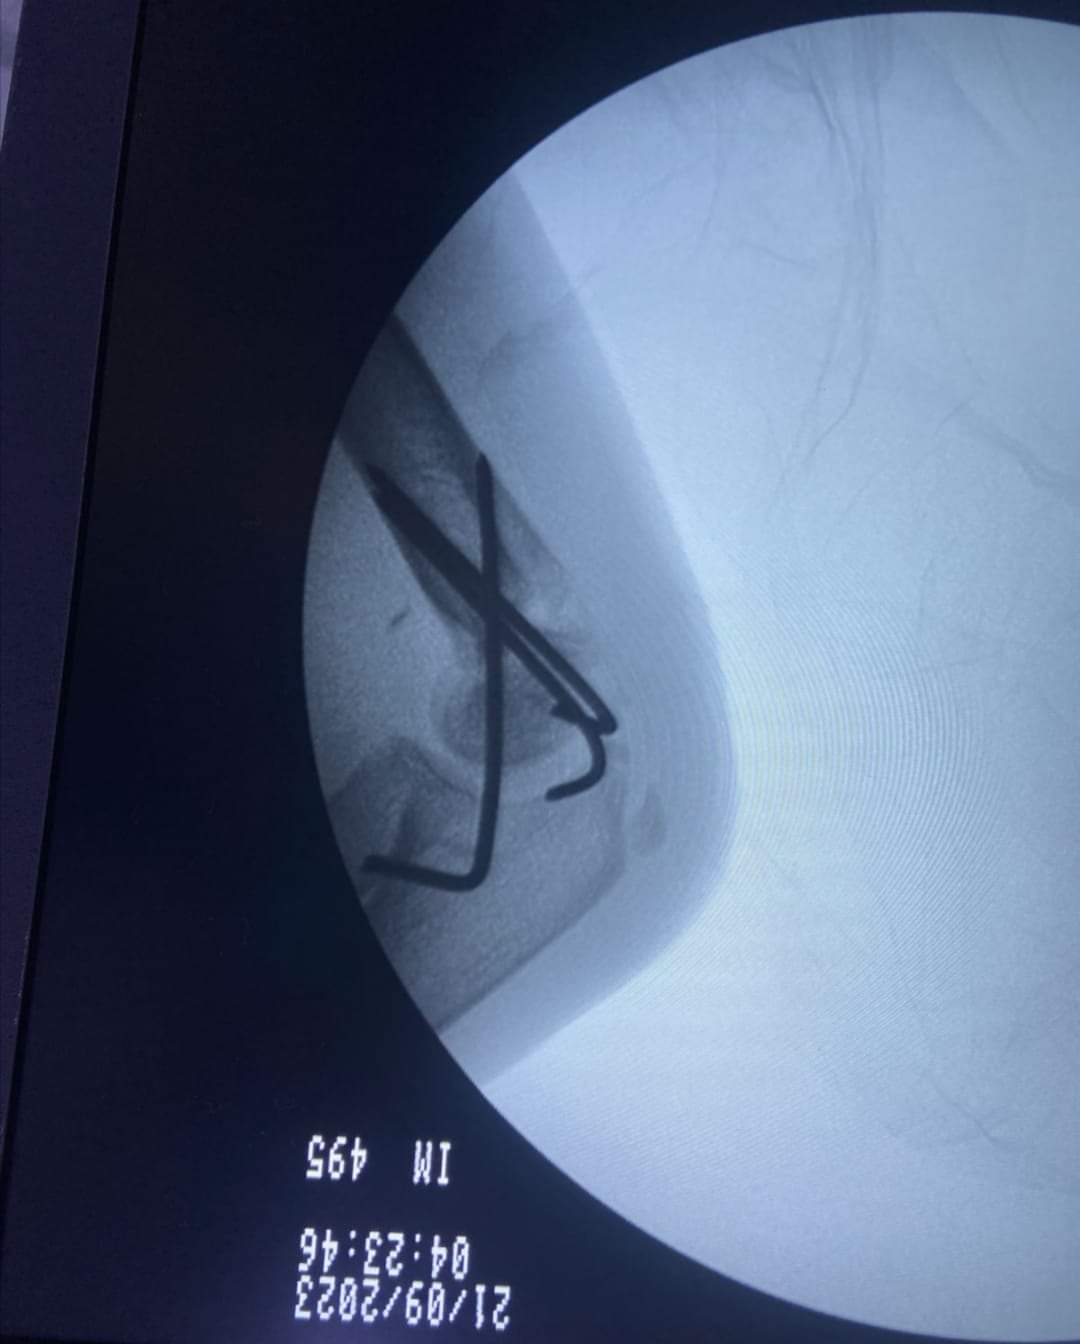

وطنا اليوم -  يقوم بعمليات تثبيت الكسور المعقدة بشكل طاريء وتبديل المفاصل بشكل مبرمج  مما خفف على المواطنين البحث عن أسرة في مستشفيات مركزية رغم صعوبة عمليات العظام من الناحية التقنية في المستشفيات النائية  إضافة الى  استقبال اعداد كبيرة بالعيادات ومعالجة جميع المرضى بالطرق المثلى انه الدكتور الانسان البارع والمتميز يزيد البريزات طبيب العظام في مستشفى الاميرة سلمى / ذيبان عيادة العظام  علماً بأنه كان  مستشفى تحويلي منذ تاسيسه والدكتور البربزات وقبل اربع سنوات في عام 2020  منذ انتقاله للمستشفى يقوم بهذه العمليات ومن بينها  عمليات نوعية لمرضى يعانون من كسور معقدة في الترقوة واجراء عمليات دقيقة ومعقدة لكسور لمرضى في مختلف أنحاء الجسم وعمليات تثبيت الكسور المعقدة وتركيب المفاصل وغيرها الكثير  والديسك " وآلامه وتبعاته وعلاجه وإجراء عمليات معقده وصعبه.

وأجرى الدكتور البريزات عمليات كبرى في جراحة العظام والتي تحتاج إلى مراكز متقدمة ومتطورة. وكذلك العمل على تثبيت أغلب انواع الكسور بطريقة طارئة وتبديل المفاصل بطريقة مبرمجة بما يتناسب مع امكانات المستشفى والتي هي  جزء من  العمليات الدورية بمستشفى الاميرة سلمى في ذيبان  والتي تخفف العبئ على المستشفيات المركزية وعلى المواطن في آن واحد.

وعبر كثير من  المرضى وذويهم عن عظيم شكر هم وامتنانهم للدكتور البريزات على ما بذله ويبذله  من جهود كبيرة واستثنائية في تعامله مع المرضى والمراجعين  ومتابعته الحثيثة لهم والاطمئنان عليهم والتي تكللت جميعها بالنجاح وله الدور الكبير   برفع كفاءة قسم العظام  بالمستشفى بشكل عام والذي  أصبح  متطوراً بالقيام بالعمليات مثل تثبيت الكسور المعقدة و تركيب المفاصل و غيرها.